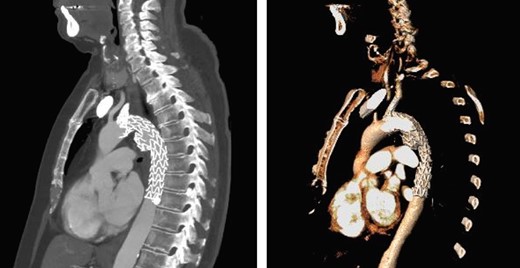

A 74-year-old woman was referred to our vascular service with a 6-month history of hoarseness of voice and intermittent dry cough. The patient’s medical history included hypertension and gastroesophageal reflux disease. Flexible laryngoscopy demonstrated a foreshortened, lateralised and flaccid vocal fold consistent with unilateral vocal cord paralysis. Subsequent computed tomography (CT) imaging of the neck and thorax revealed a saccular aneurysm in the aortopulmonary window measuring 39 mm (Fig. 1). Digital subtraction angiography confirmed the presence of a ductal aneurysm with a well-defined neck and no intraluminal thrombus (Fig. 2). There was no contrast extravasation into the mediastinum or pulmonary circulation. Following a cardiovascular multidisciplinary meeting, treatment options were discussed with the patient and consensus favoured endovascular repair. The distance from the proximal margin of the aneurysmal neck to the origin of the left subclavian artery measured just under 2 cm and therefore did not meet the manufacturer’s minimal landing zone requirements. To circumnavigate this dilemma, a left subclavian stent graft was inserted with its proximal end parallel to the main thoracic endoprosthesis. The procedure was uncomplicated and repeat imaging revealed widely patent stent grafts with satisfactory positioning and absence of endoleak (Fig. 3). Our patient was discharged home on the second postoperative day. She continued speech and language therapy postoperatively and has made remarkable recovery of phonation, declining any further treatment options for same.

Sagittal CT with 3D reconstruction at 1-year post-intervention, showing satisfactory placement of stent grafts.